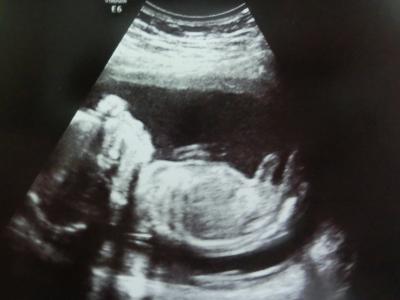

Huhu ihr lieben, hatte heute Termin bei der Frauenärztin.. Es ist alles in Ordnung und prima Unser Buzi ist nun wohl etwa 22 cm groß und wiegt stolze 340 Gramm Eindeutig konnte sie das Geschlecht nicht erkennen, aber sie denkt, dass unser Buzi eine kleine Prinzessin ist Am 27.6. ist die Feindiagnostik, mal schauen ob's dabei bleibt

Bild zu Kein Outing, dafür 'ne Schätzung =D - Forum für November - Mamis